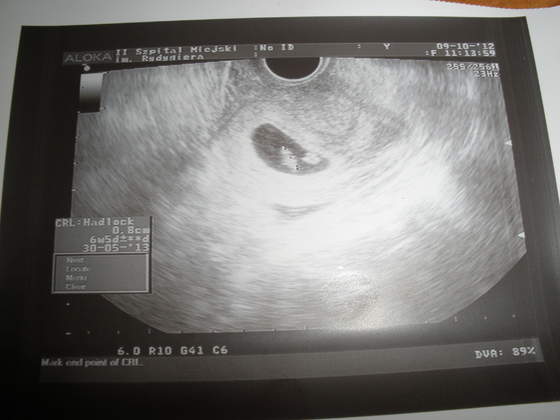

Dziewczyny melduje się Wczoraj nie pisałam bo miałam tylko badanie paluchami i potwierdzenie ciąży. Za to dziś po 11 miałam usg Fasolka ma się bardzo dobrze, a co najważniejsze serduszko bije ) Termin porodu mam na 30.V.2013, czyli tydzień później niż z OM, tak samo jeśli chodzi o tygodnie ciąży bo według lekarza mam 6 tydz 5 dz. Moje malutkie szczęście ma 8 mm